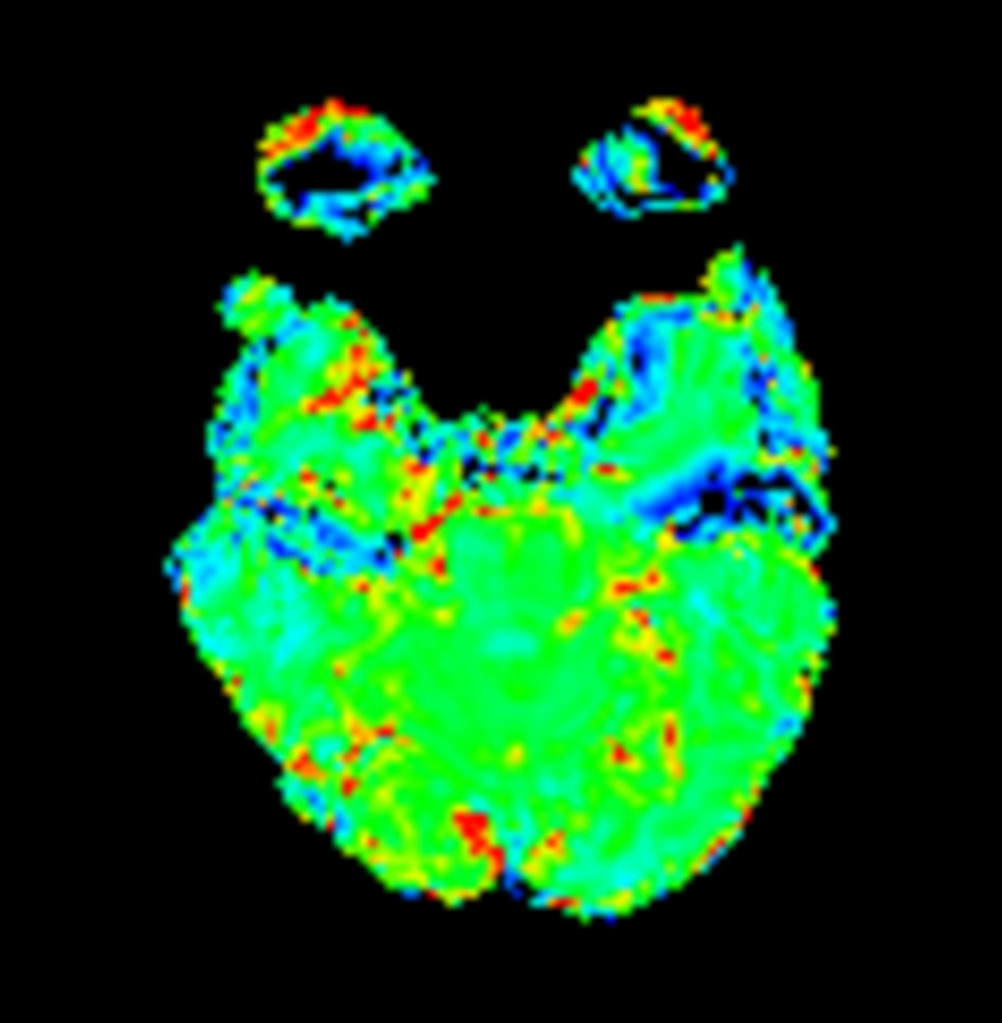

Axial T2* Perfusion (Index)

-